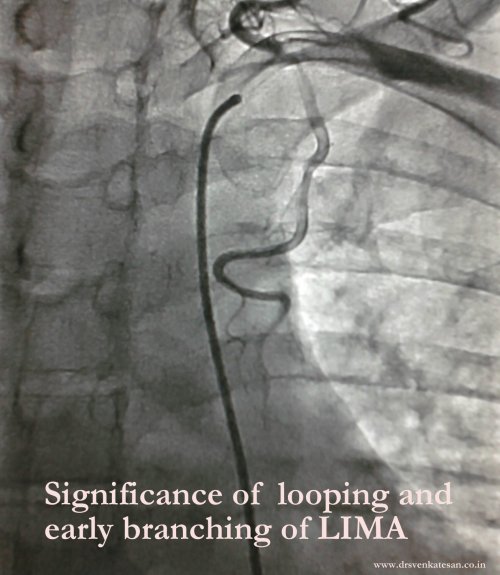

Looping of LIMA is rarely an issue in hemodynamic point of view. But some believe a looped up LIMA is slightly prone for graft disease.Complex looping are reported rarely.

A loop and a early branch of LIMA : What is the implication ?

Abnormal or premature branching pattern of LIMA needs clipping as it may divert blood supply to LAD.Terminal branches can be used as a sequential graft to a branch of LAD usually a diagonal. In spite of all these issues , LIMA is rarely unsuitable either anatomically or physiologically .It is a safest vessel to graft.